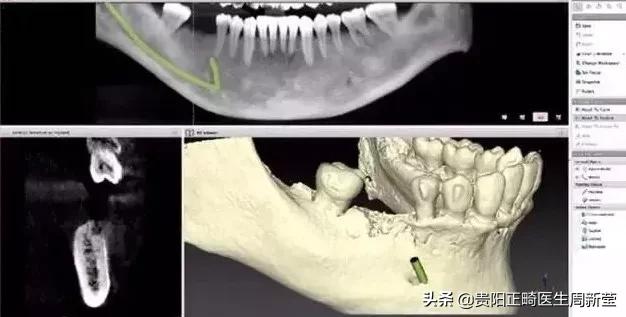

要知道医生的眼睛不是透视镜,牙齿好比大树,树根扎在土壤里,而我们的牙根也埋在牙槽骨里,牙根的状态、里面的神经肉眼都是看不到的。

只有通过牙片,牙医才可以确切了解龋坏的范围、牙痛是由牙髓炎还是根尖炎或是牙周炎引起、种植牙需要的骨量等等。

牙片为医患沟通提供了准确的依据。